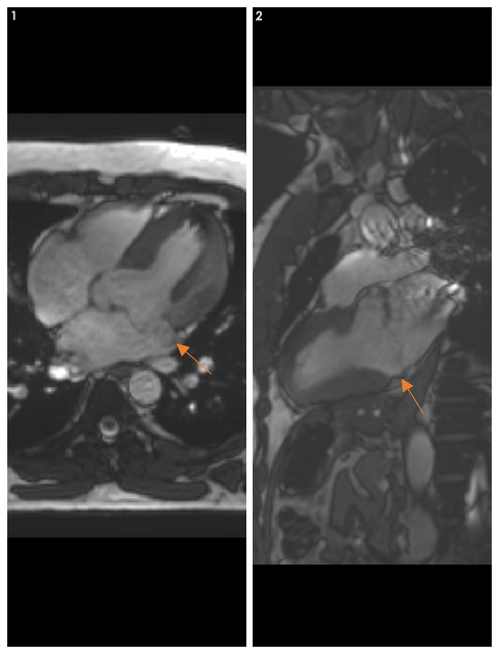

Figura 1: imagini statice 2 camere și 4 camere din achiziţie cine-SSFP cu sincronizare ECG

Figura 2: cardioRM achiziţie postcontrast triplă inversie-recuperare în axul scurt biventricular

Discuţie caz nr 96: Boală Barlow este un sindrom clinic datorat prolapsului de valvă mitrală; se evidențiază deplasarea în sistolă a cuspelor mitrale spre atriul stâng ce asociază disjuncţie de inel mitral și fenomen de curbare posterioară. Această forțare a miocardului ventricular stâng din segmentele laterale poate duce la apariția de arii de fibroză că substrat aritmogen – materializate sub formă de priză de contrast (nu e cazul la acest pacient).